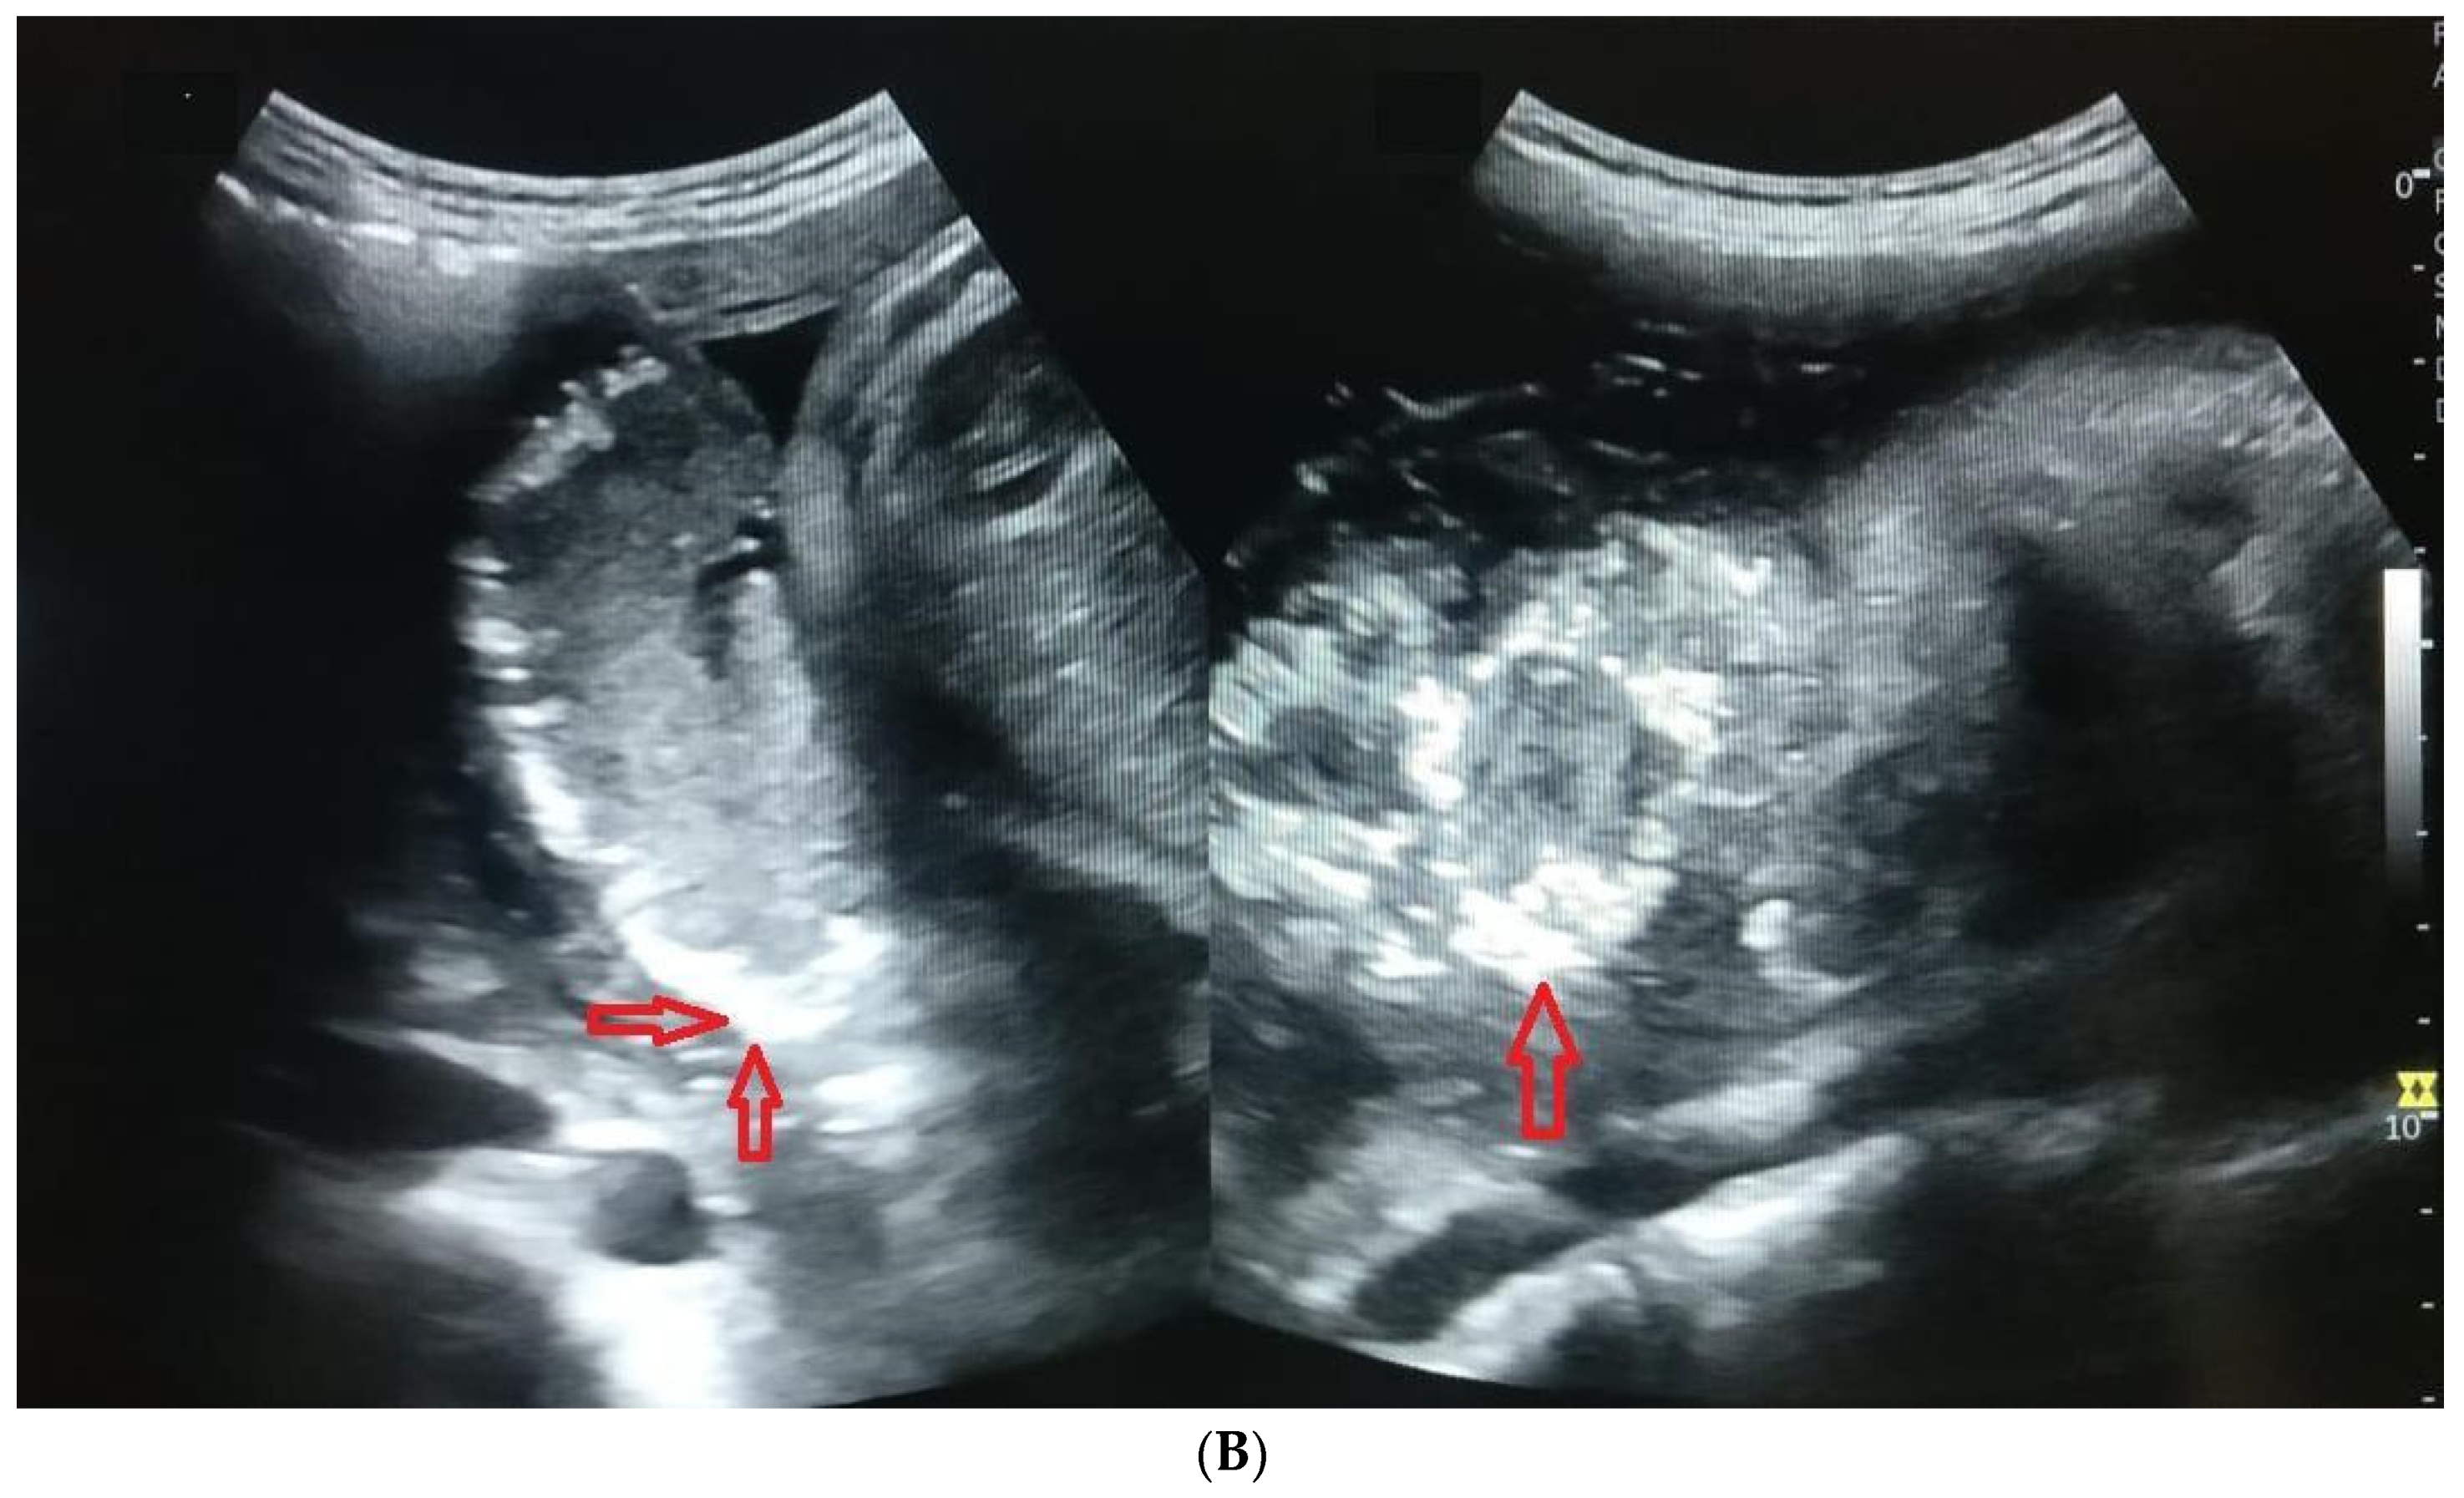

Ultrasound was performed to document the cases of PPC from 28 weeks of gestation at every four-week interval. Echogenic indentation from the chorionic plate to the basal layer dividing the placenta into random lobules, similar to cotyledons, was considered Grade III placental calcification (Figure 2A,B). A doppler flow study was conducted starting from 32 weeks of gestation to 36 weeks at an interval of 4 weeks. The ultrasound equipment used for this study was a Siemens Acuson × 300 PE USG machine with a curvilinear transducer and a frequency of 1.9 to 6.4 MHz, analyzed by a single consultant in order to avoid interobserver bias. The images were verified by another senior consultant to ensure the accuracy of diagnosis. Both the consultants were obstetricians trained in ultrasonography. In the umbilical artery Doppler study, absent or reversed end-diastolic velocity (AREDV) was considered to reflect poor uteroplacental blood flow. The other Doppler indices measured were the umbilical artery pulsatility index (Umb PI) ≥ 95th, middle cerebral artery pulsatility index (MCA PI ≤ 5th), cerebro placental ratio (CPR ≤ 5th), Mean uterine PI ≥ 95th, and unilateral or bilateral notch in the uterine artery.

Figure 2.

(A) Image showing placental calcification and lobulation (grade 3 placenta) in a case of 26-year-old primigravida at a gestational age of 33 weeks and 6 days. Red arrows show the placental calcification and blue arrows show lobulations. (B) Image showing grade 3 placental calcification in a 31-year-old primigravida at a gestational age of 35 weeks and 1 day. Red arrows show the placental calcification.